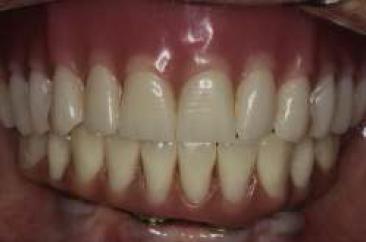

Al tercer día se realizó la instalación con torque manual y ajuste oclusal (figs. 13,14,15,16).

A los 10 días, luego de la cirugía, se citó a la paciente a control para realizar la retirada de la sutura11; se dio torque a los tornillos protésicos (10 N/cm) y se chequeó la oclusión nuevamente. Se ha seguido controlando a la paciente cada 6 meses, hasta cumplir 2 años desde la fecha de instalación de la aparatología, sin manifestar complicación alguna (figs. 17, 18, 19, 20, 21).

Se puede observar un control adecuado de biofilm por parte de la paciente.